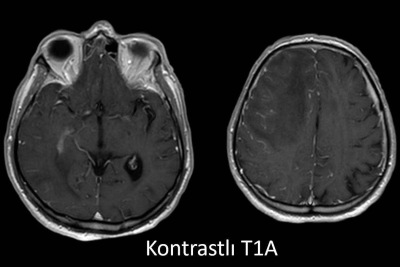

- D) Kontrastlı T1A sekansta hafif leptomeningeal boyanma (sarı ok).